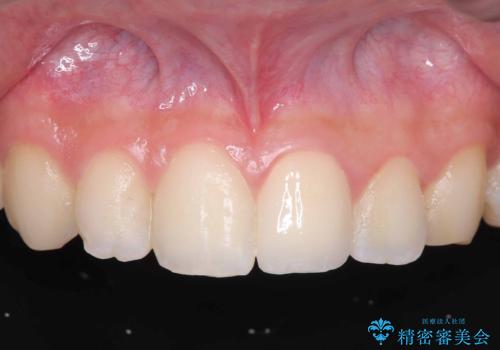

神経の状態が良好に保たれていることを確認した後、オールセラミッククラウンによる審美修復を行いました。

なお、最終補綴前にはオフィスホワイトニングを実施し、より自然で明るい仕上がりを得ることができました。

他院では「治療が難しい」と言われた患者様でしたが、当院で神経を残すことができ、見た目もきれいに仕上がったことで大変喜んでいただけました。